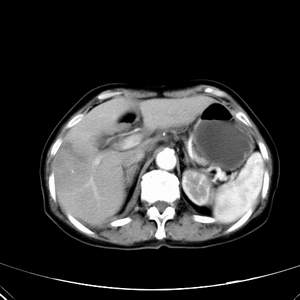

患者,女性,77岁,右上腹胀痛月余。afp正常。ca125升高。即往无肝炎病史。

肝右叶病灶是胆管细胞癌吗?门静脉右支癌栓形成?右侧肾上腺有问题吗?

快进快出符合肝癌表现

最后5幅图片是延时7分钟的。门静脉右前支内有充缺吗?如有,肝血管瘤不好解释。

病灶渐进性向心性强化,延时病灶中心见条片状高密度影,局部见肝包膜回缩征,结合病人无肝炎病史,考虑肝右叶胆管细胞癌,门脉右支癌栓形成。